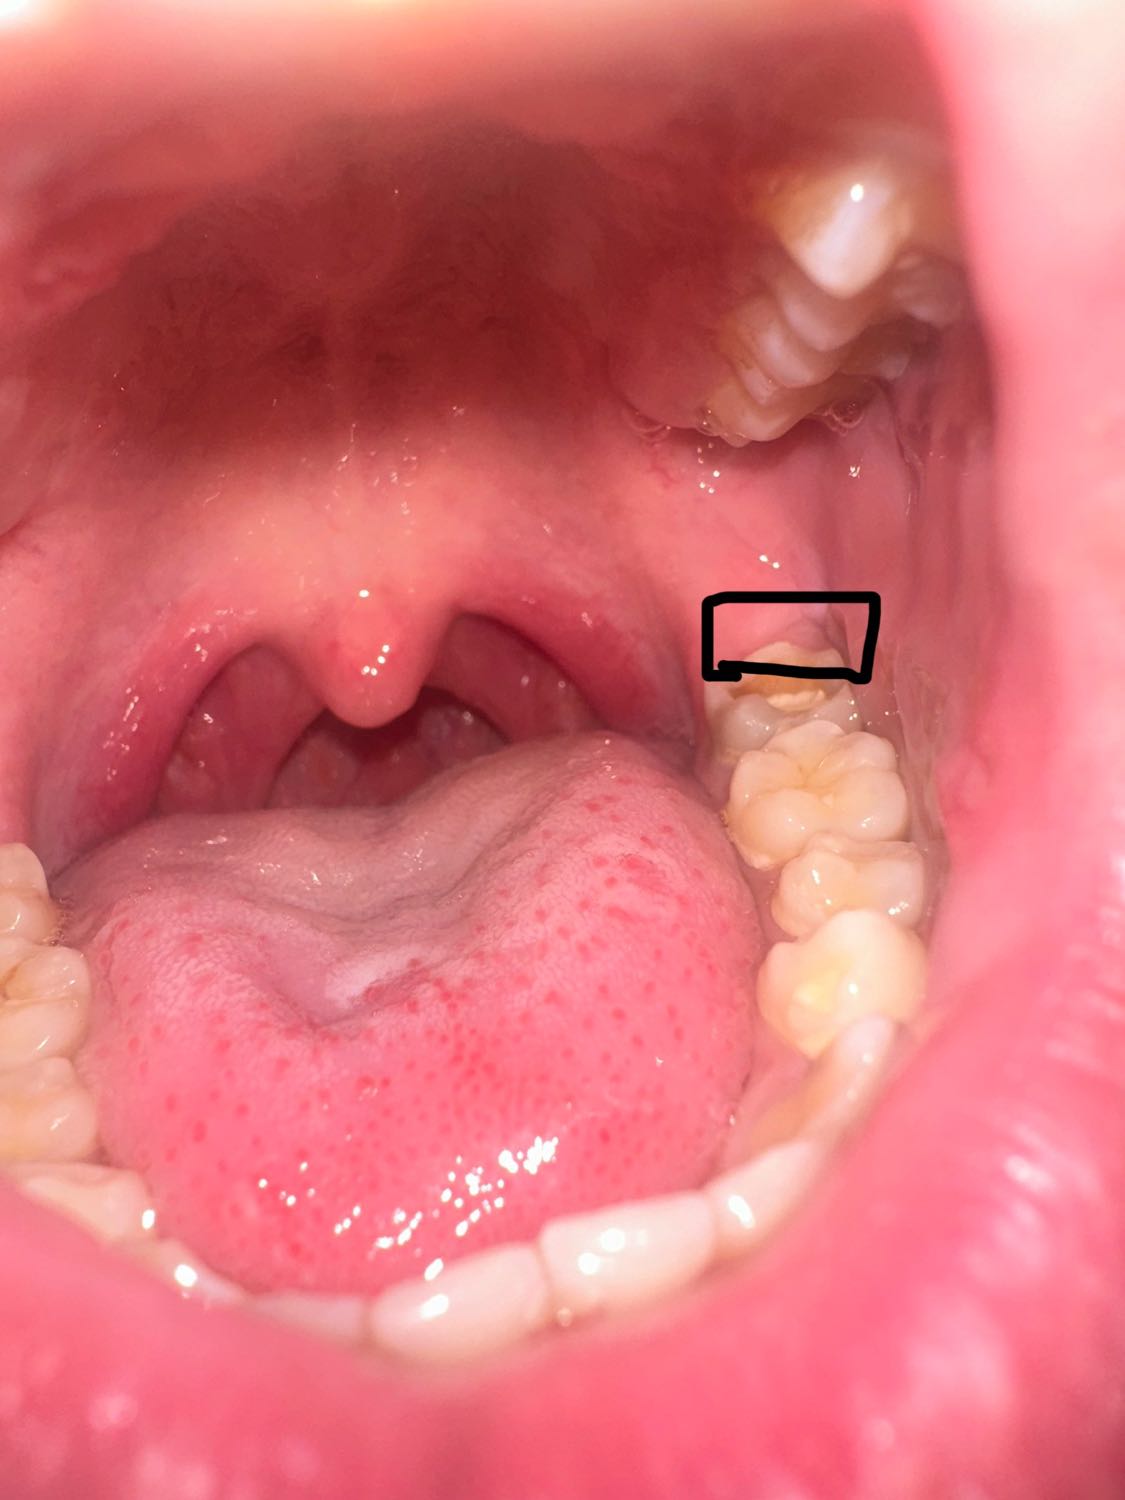

หลังฟันกรามบวมหรือไม่ แต่ทำไมไม่เจ็บ